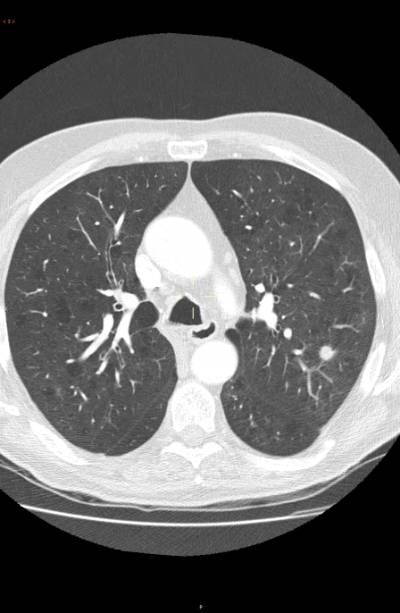

"El cáncer puede ser detectado en estadios más precoces utilizando la tomografía computarizada de baja radiación. Esta prueba permite identificar el cáncer en un estadio precoz, cuando se presenta en forma de un pequeño nódulo en el pulmón y antes de que se extienda a otras partes del cuerpo. Esta tecnología ha aumentado la tasa de curaciones", detalla el doctor José María Echave-Sustaeta, jefe de departamento de Neumología del Complejo Hospitalario Ruber Juan Bravo y del Hospital Universitario Quirónsalud Madrid.

El cribado con tomografía computarizada de baja radiación ha conseguido una detección de tumores en estadios precoces. "En la actualidad sólo un 15 por ciento de los carcinomas no microcíticos de pulmón permiten una intervención curativa; mientras que en los programas de cribado mediante tomografía computarizada han conseguido la detección de entre un 65 y un 85 por ciento de tumores en estadios precoces", detalla el doctor Echave-Sustaeta, que considera que las personas que están en el grupo de alto riesgo de cáncer deberían realizarse la prueba una vez al año.

La utilización de tomografías computarizadas de baja radiación expone al paciente a una dosis de radiación muy pequeña (el equivalente a una cuarta parte de la radiación que una persona recibe de fuentes naturales durante un año).